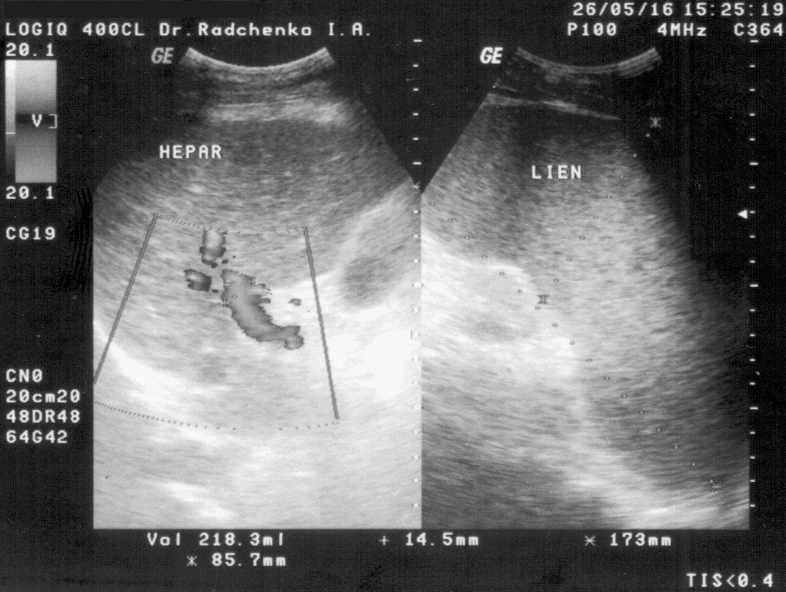

Прошёл рентген лёгких. Результат: в лёгких воспаления нет, рака нет, есть немного бронхит; сердце без патологий. Прошёл УЗИ ОБП, результат завтра отсканирую и выложу позже. Сдал ОАМ и ОАК. И так, со слов УЗИ-стки. То, чего нет в заключении УЗИ ОБП. Женщина прониклась моей историей и подчерпнула для себя немного нового. Заглянула мне в лёгкие, нашла там плевральную жидкость, но совсем не много, поэтому на рентгене могли просто не заметить. Согласилась, что правильно сделал, что купил и колю цефтриаксон. Было бы лучше его проколоть ещё в терапии, т.к. капали ещё и детоксикационное. Дозировку я для себя выбрал верную, 1гр через 12 часов, т.к. цефалоспорины держутся в организме около 12-ти часов. Это раз, второе 1гр при циррозе вполне мягко для ЖКТ, но пробиотики всё-равно нужны. Я ем йогурт в капсулах, 2 капсулы перед каждым приёмом пищи. Так сказать, дрыщь